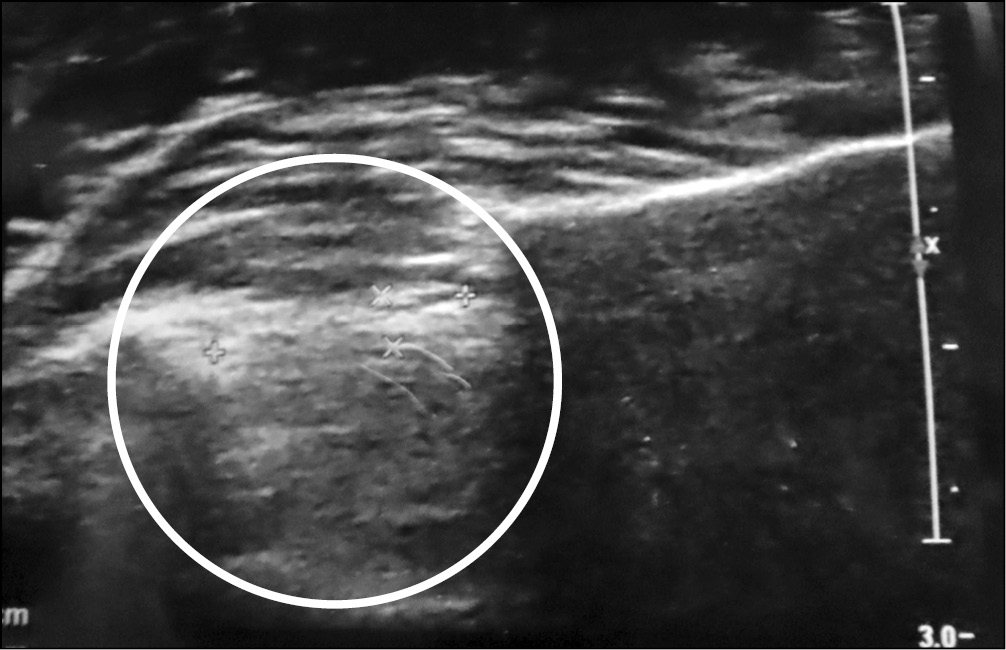

Дистальный отдел межкостной мембраны так же визуализируется, как гиперэхогенное образование. У людей, у которых отсутствует ДКП, толщина ДММП составляет от 0,3–0,7 мм в независимости от положения предплечья (рис. 8). Толщина же ДКП при УЗ-исследовании составляет от 0,9 до 2 мм также в независимости от положения предплечья (рис. 9). Среднее значение составляет 1,4 ± 0,5 мм. Из 30 обследуемых дистальный косой пучок был выявлен у 13 женщин (92,8 %) и 1 мужчины (7,1 %), что в процентном соотношении составило 43 %. Помимо ширины измеряли и длину ДКП, интервал длины у обследуемых составляет от 13 до 19 мм. Среднее значение 15,5 ± 1,9 мм. Изменение длины также не происходит независимо от положения предплечья.

Рис. 8. Ультразвуковое изображение дистального отдела межкостной мембраны предплечья — дистальный косой пучок не определяется

Рис. 9. Ультразвуковое изображение дистального отдела межкостной мембраны предплечья — дистальный косой пучок присутствует (показано стрелкой)